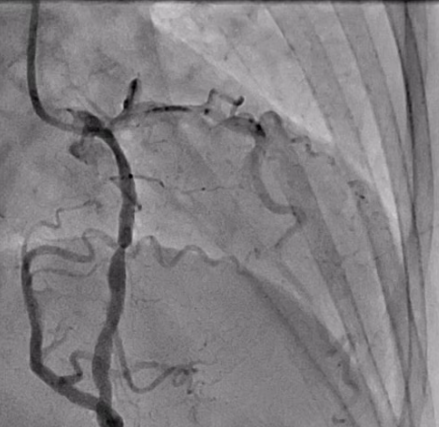

Via transradial access, diagnostic coronary angiography was performed and a 6 French Judkins left (JL) 3.5 diagnostic catheter was used to selectively engage the left coronary artery. A 6 French 3D right curve (3DRC) diagnostic catheter was used to selectively engage the anomalous RCA originating from the left sinus. Diagnostic coronary angiography demonstrated a severe lesion in the proximal RCA that was the culprit of the patient’s presentation. A 6 French JL 3.5 guiding catheter was used to engage the anomalous RCA. We were able to successfully perform PCI with deployment of a 4.0 mm drug-eluting stent in the proximal RCA with excellent angiographic results, minimizing usage of contrast, radiation time, and avoiding excessive catheter exchanges (Videos 1-5).

Selective angiography of anomalous coronaries can be challenging and time-consuming. The acute angle take-off of the origin of an anomalous RCA may pose further challenges to selective engagement and coaxial guide seating, and may not provide the adequate guide catheter support required for a successful PCI. Based on a current review of the literature, a variety of different guiding catheters have been used for PCI to an anomalous RCA.3 We used a JL3.5 guide catheter as it was able to selectively cannulate the ostium of the anomalous RCA from the left cusp. It is important to be aware of the usage of different techniques and guiding catheters to adequately engage the uncommon anomalous coronary for a successful PCI, especially during myocardial infarction (MI) presentations, given that in an acute MI, if an anomalous vessel is the culprit, such technical challenges can potentially delay the door-to-balloon time.